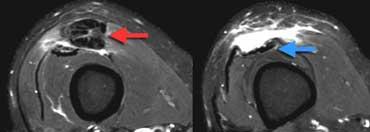

TRÁI: Dập xương lồi cầu ngoài (vòng tròn vàng). MCL bình thường (mũi tên xanh lá) nhưng không thấy dây chằng xương bánh chè – lồi cầu đùi phía trước. PHẢI: Dây chằng xương bánh chè – lồi cầu đùi phía trong bị đứt khỏi điểm bám tại xương đùi.

Ca bệnh bên trái là một nữ cầu thủ bóng đá bị xoắn vặn khớp gối.

Bốn hình ảnh MRI từ dưới lên trên thể hiện đầy đủ các đặc điểm hình ảnh của trật khớp xương bánh chè kèm đứt dây chằng xương bánh chè – lồi cầu đùi phía trong.

Xương bánh chè bị trật và mặt khớp phía trong đã va đập vào lồi cầu ngoài xương đùi.

Xương bánh chè đã tự trở về vị trí bình thường.

Tổn thương dập xương có thể kèm theo biến chứng gãy sụn khớp.